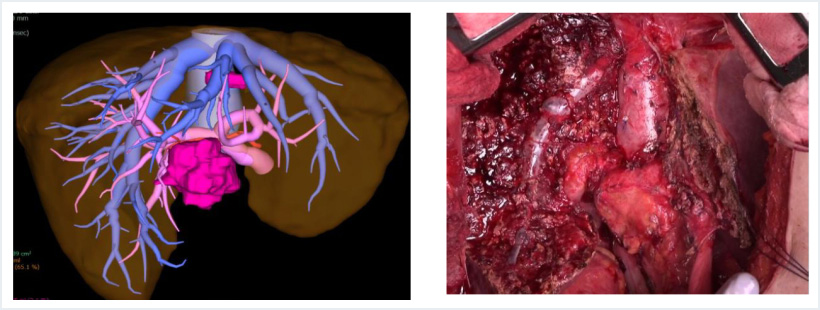

①開腹肝切除

開腹肝切除は大きな傷が必要になりますが、あらゆる処置を直視下に確実に行うことが可能であり、不意な出血にも対応しやすいために、複雑な肝切除や大きい腫瘍の切除の多くは開腹手術をおこなっております。当チームでは、肝移植の知識、技術を生かし、他施設で手術困難な脈管浸潤のある進行癌症例の手術も数多く行っています。

【大腸癌肝転移に対する中央二区域切除+尾状葉切除】